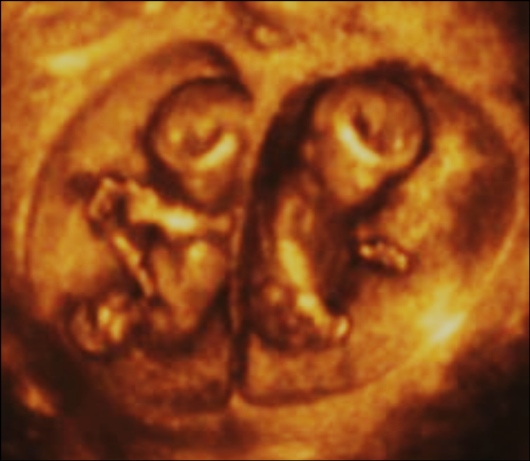

Третья беременность двойней

Третья беременность двойней 139 фотографий